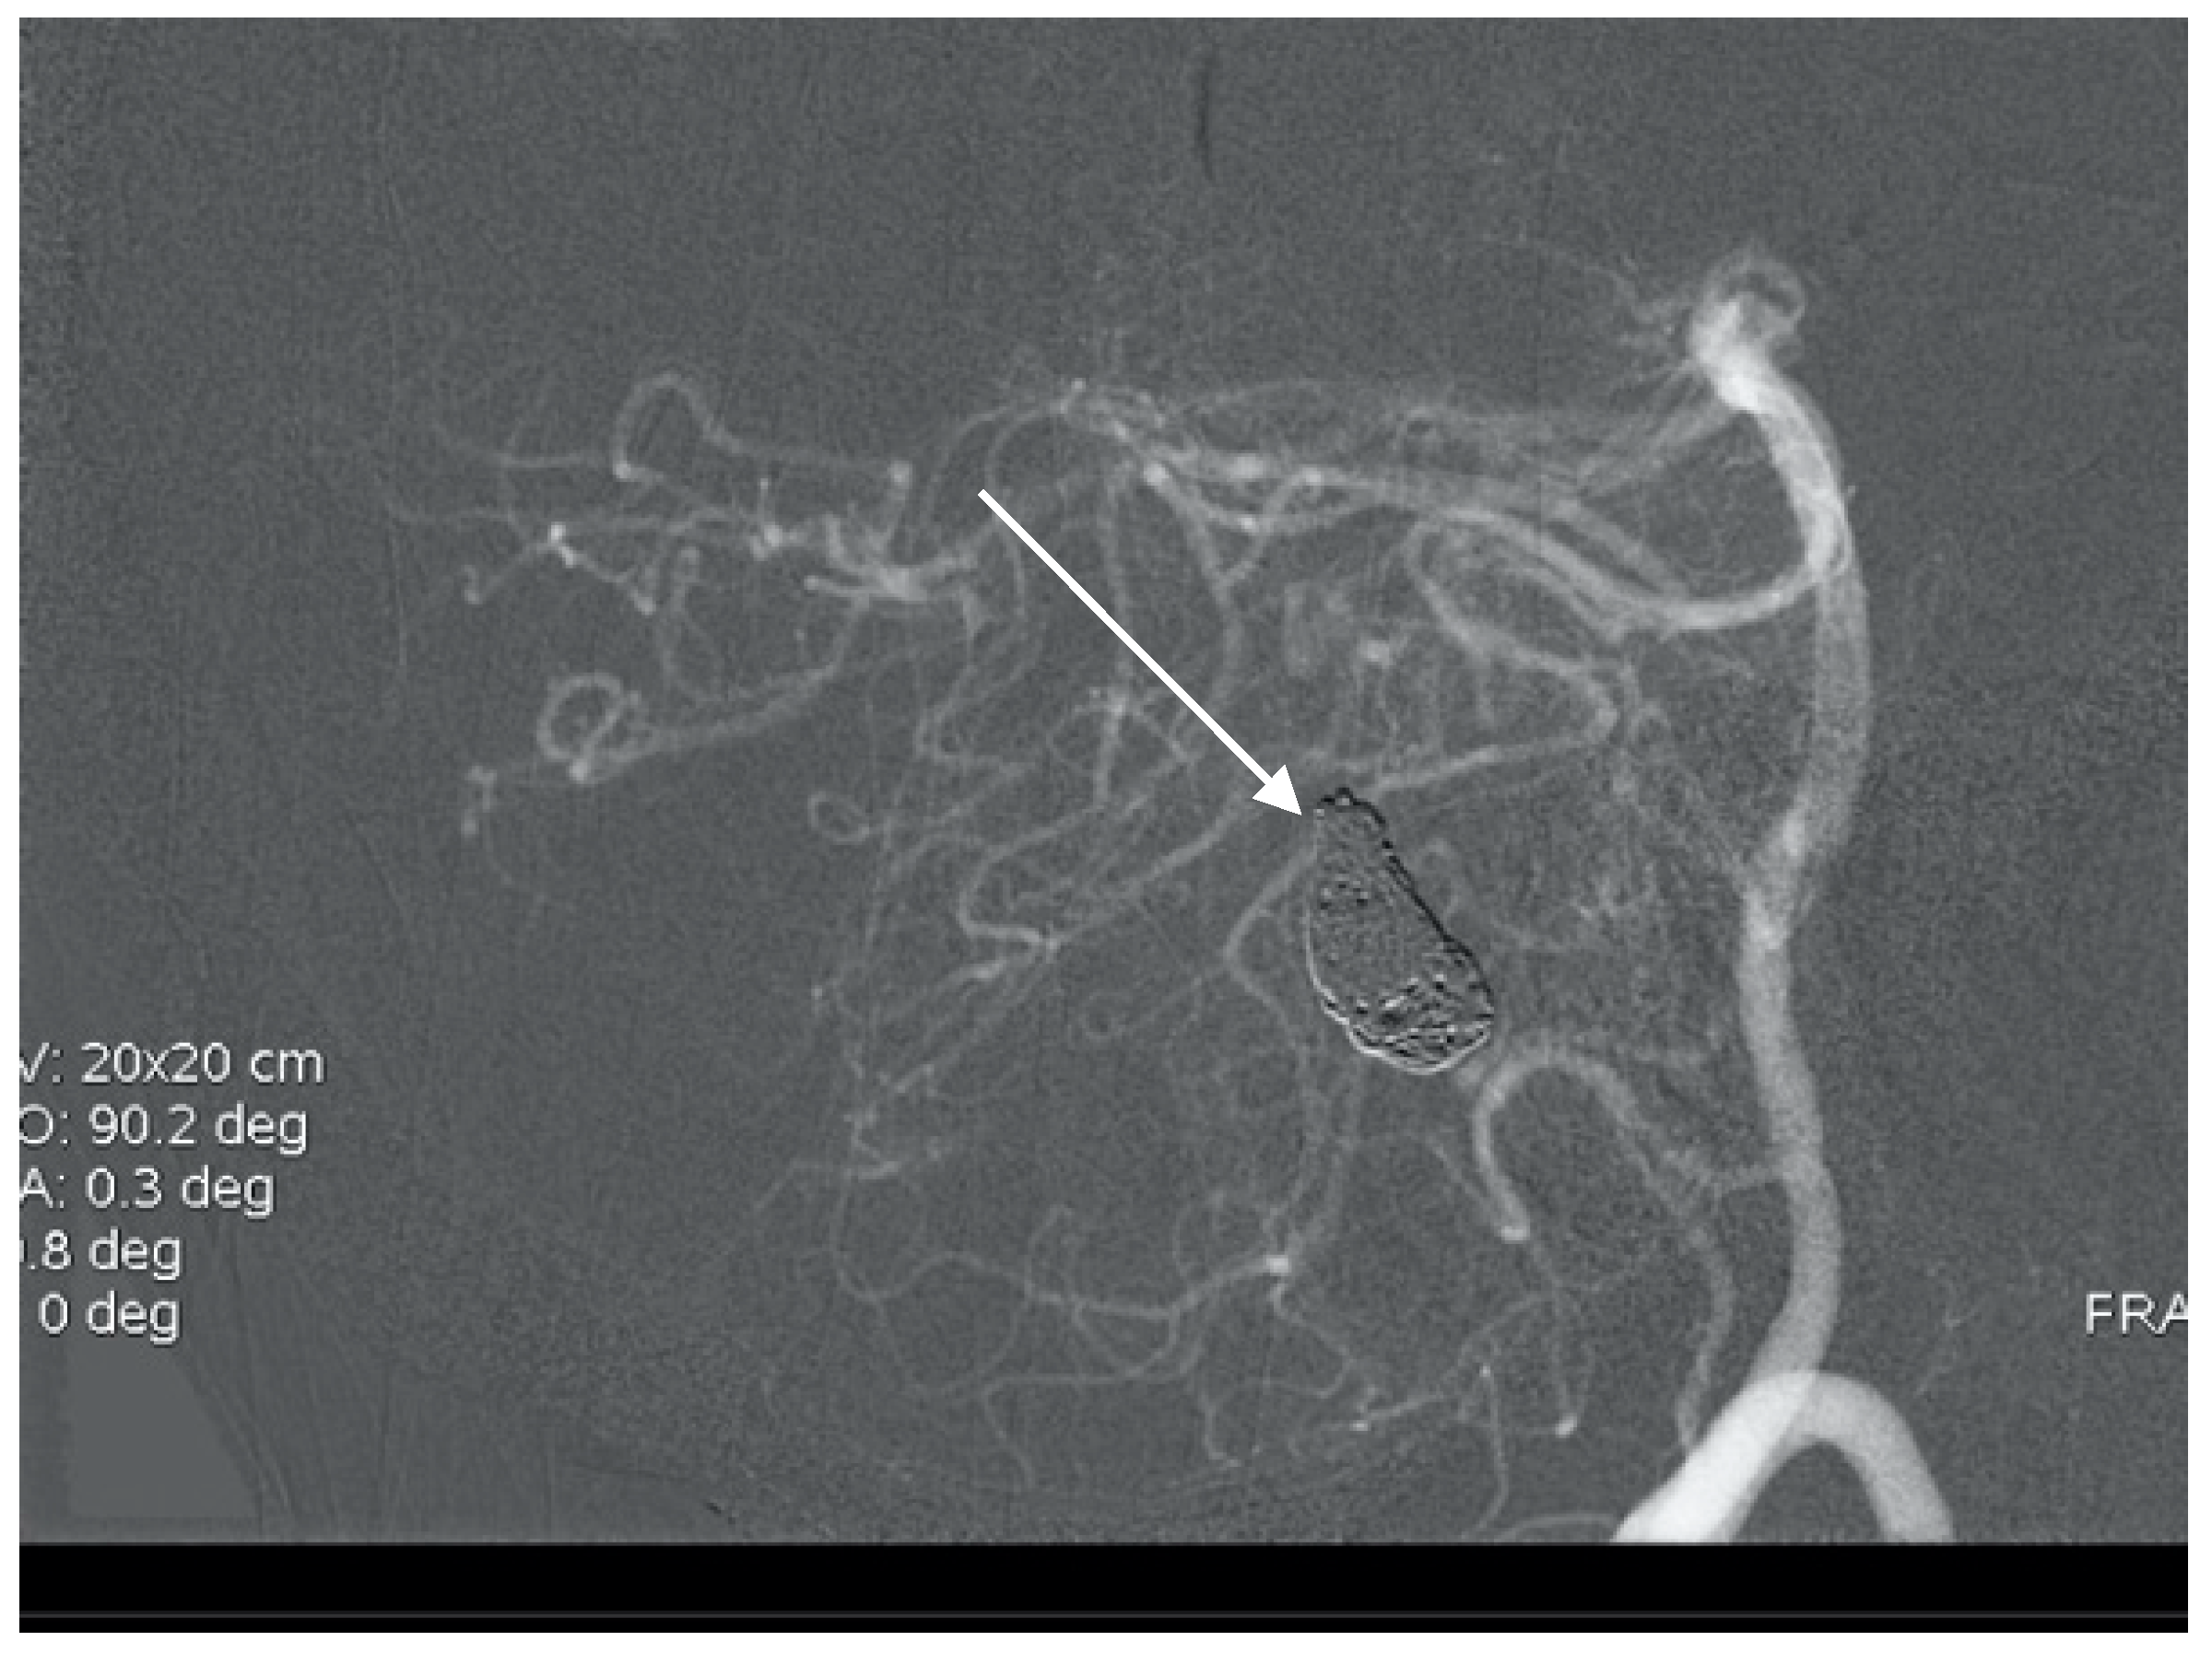

A 60-year-old woman was admitted for abrupt loss of consciousness. CT in a peripheral setting showed cerebellar hemorrhage with a pan-intraventricular hematoma in the fourth ventricle and a massive SAH in the cerebellar and spinal canal regions (Figure 4). AG revealed three aneurysms on the distal PICA (Figure 5), successfully excluded from circulation by microsurgery clipping while maintaining patency of the PICA. During the surgery, sudden intraoperative rupture occurred from the most peripheral aneurysm, located just under the arachnoid membrane on the surface of the cerebellum. After easy clipping of the neck, the feeding vessel was followed in the hematoma to its telovelotonsillar part, where another two aneurysms were visible. With the technique of temporary clipping, the optimal final position on both clips was achieved in the wide necked aneurysms. The patency was confirmed with intraoperative ultrasound. A difficult postoperative course and hydrocephalus required temporary ventricular drainage, which was converted to a ventriculo peritoneal (VP) shunt with a good long-term result.

Figure 5. Oblique projection of an angiogram with three PICA aneurysms.